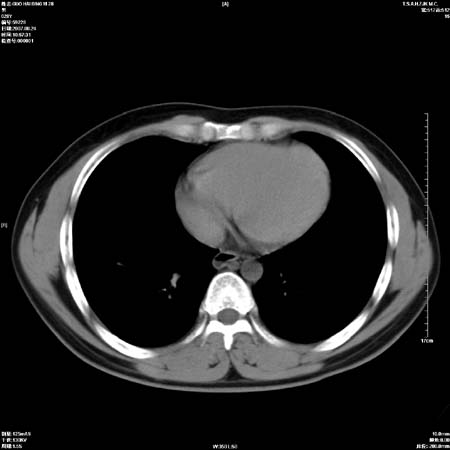

左肺门区软组织肿块,左肺上叶支气管开口消失,纵隔内见肿大淋巴结,考虑左中心型肺部,可以做纤支镜取病理确认.

左肺肺门区肿块影,分叶明显,左肺上叶支气管开口受压,纵隔内见肿大淋巴结,考虑左中心型肺癌。

支持左上叶中央型肺癌伴纵隔淋巴结转移.

左上叶中央型肺癌伴纵隔淋巴结转移

左上叶中央型肺癌伴纵隔淋巴结转移.

肿块形态影像支持左上叶中央型肺癌伴纵隔淋巴结转移。

支持左上叶中央型肺癌伴纵隔淋巴结转移

支持左肺上叶中央型肺癌伴纵隔淋巴结肿大.

左侧中心型肺癌纵隔淋巴结转移。我们见一例16岁男孩,已经脑转移了。

肺癌并纵隔淋巴结转移。

左上叶中央型肺癌伴纵隔淋巴结转移.苦命!

左肺中心型肺癌并纵隔淋巴结转移!考虑为小细胞肺癌,没有手术机会了,只能进行放化了,疗效不错,但极易复发。没办法,现在肿瘤年轻化越来越明显了。

左上肺癌伴纵隔淋巴结转移.